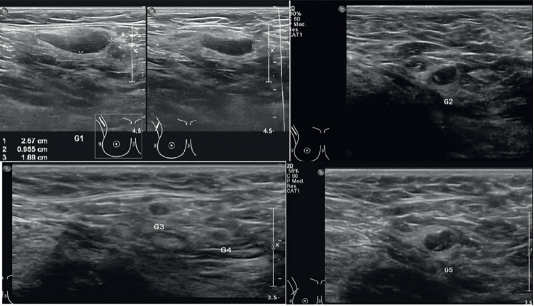

Debido al compromiso ganglionar axilar, se realizó una ecografía mamaria que evidenció ganglios con pérdida de su morfología habitual (figura 5). En consecuencia, se propuso una disección radical axilar derecha, programada para el 14 de septiembre de 2023 en conjunto con el servicio de cirugía plástica. Posterior a la resección ganglionar, las muestras fueron enviadas al servicio de patología, donde se confirmó la afectación tumoral de los ganglios extraídos. El paciente continuó con ciclos de quimioterapia con cisplatino y 5-FU, logrando la resolución completa de la enfermedad. Se programó control por servicios multidisciplinarios con estudios de imagen, evidenciando que el paciente se encontró libre de enfermedad para octubre del 2024.

En el caso presentado, el diagnóstico se estableció mediante tomografía computarizada, evaluación clínica y análisis del tiempo de evolución. Se realizó una escisión quirúrgica con análisis histopatológico posterior, que confirmó el diagnóstico de pilomatrixcarcinoma. Este caso es particularmente relevante debido al compromiso ganglionar ipsilateral, evidenciado mediante ecografía de ganglios axilares derechos. Los hallazgos ecográficos incluyeron pérdida de la relación córtico-medular, desplazamiento del hilio graso, engrosamiento cortical (> 3 mm) y vascularidad periférica en Doppler. Estos hallazgos corroboran el compromiso ganglionar del pilomatrixcarcinoma3.